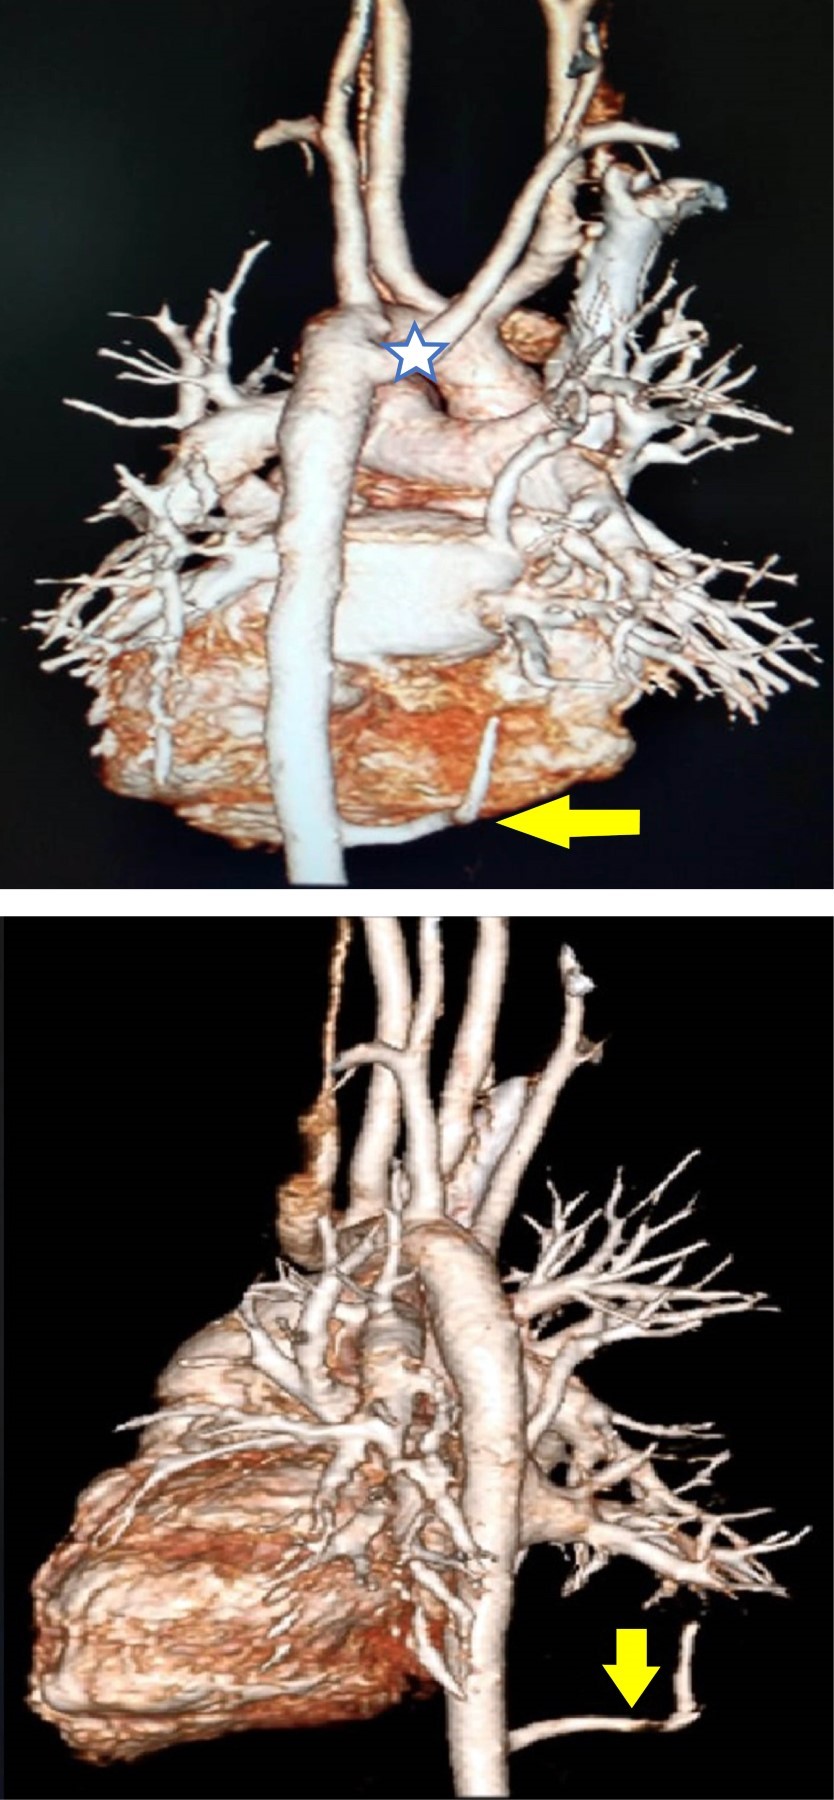

Estudios: difusión de monóxido de carbono (DLCO) 7.5 mL/min/mmHg (valor predicho 10.2), espirometría posbroncodilatador con una respuesta en volumen espiratorio forzado en el primer segundo (FEV1) del 16% y de más de 200 mL. La radiografía de tórax muestra un patrón atelectásico (Figura 1). Serie esofagogastroduodenal (SEGD) con presencia de reflujo grado III; en la angiotomografía de tórax (angio-TC) se observa una subclavia derecha aberrante (Figura 2), lo mismo que en la aorta descendente, también un vaso aberrante (Figuras 3 y 4).

Por otra parte, las técnicas de imagen son pruebas complementarias que confirmarán el diagnóstico. La radiografía de tórax puede proporcionar información sobre el desplazamiento del arco aórtico o la tráquea, la presencia de una estenosis traqueal, así como infiltraciones pulmonares, distelectasias o atelectasias como signos de compresión de las vías respiratorias.9 El esofagograma muestra la indentación esofágica; sin embargo, la información anatómica obtenida no es lo suficientemente precisa para el tratamiento terapéutico, por lo que se requieren imágenes transversales como la tomografía computarizada (TC) o la resonancia magnética (RM). Se pueden usar métodos de posprocesamiento para generar datos 3D, tanto de la TC como de la RM, dando una vista detallada de la morfología vascular.10 En cuanto a los estudios de radiología la SEGD no reveló identaciones esofágicas, sólo la presencia del reflujo severo; tampoco la tele de tórax mostró imágenes radiológicas sugerentes de las malformaciones, por lo que no fueron concluyentes para el diagnóstico. Por lo tanto, la TC de tórax y la angiotomografía son los estudios de elección para el diagnóstico de los anillos vasculares y de las malformaciones pulmonares como lo es el secuestro pulmonar intralobar o extralobar, la otra patología agregada en nuestro paciente.

En cuanto al secuestro pulmonar intralobar y su asociación con este síndrome no existe bibliografía a nivel mundial que los relacione en una entidad común. El secuestro pulmonar es una malformación congénita broncopulmonar poco frecuente caracterizado por un segmento anormal pulmonar irrigado por una arteria aberrante de origen sistémico, en 95% de los casos se ubica en el lóbulo inferior izquierdo, representan de 0.15-6.4% de todas las malformaciones pulmonares congénitas.11,12 La incidencia anual estimada es de 30 a 42 casos por 100,000 habitantes.13 Es frecuente que se asocien con otras anomalías congénitas como la hernia diafragmática o la cardiopatía congénita.14 Se clasifica en intralobar y extralobar de acuerdo con la ausencia o presencia de una cubierta de pleura visceral independiente en tejidos pulmonares anormales.12 El secuestro intralobar es más común, se presenta en 75% de los casos.13 Estas estadísticas hacen de este caso algo poco común, puesto que a pesar de que el secuestro pulmonar intralobar es más común, la localización derecha puede hacer más difícil su diagnóstico.

Los síntomas de esta enfermedad son atípicos y tienden a diagnosticarse erróneamente, los pacientes presentan cuadros repetitivos de neumonías. Se ha descrito neumotórax de repetición, bronquitis obstructiva y dolor torácico, aunque menos frecuentes.13 En las radiografías de tórax, el secuestro intralobar puede contener aire, suelen ser más heterogéneos y menos definidos y pueden imitar una neumonía o un absceso pulmonar. En las tomografías se puede observar una masa quística con contenido aéreo o líquido, enfisema focal e hipervascularización del tejido afectado.13 La presencia del vaso anómalo se demuestra con tomografía con contraste intravenoso en 72% de la aorta torácica descendente, de la aorta abdominal, el eje celíaco o la arteria esplénica (21%), arteria intercostal (3%) y rara vez a través del subclavio, torácica interna y arterias pericardiacofrénicas.15 Tal y como se ha mencionado, los estudios radiológicos son sumamente importantes y aunque la radiografía no fue concluyente para el diagnóstico de este caso, la angio-TC sí lo fue acorde a lo que marca la literatura, en donde se observó un aumento en la hipervascularización, así como la presencia de un vaso anómalo de la aorta torácica descendente. El tratamiento de consenso para los secuestros intralobares y extralobares es la remoción quirúrgica.11-15 Este paciente se encuentra en espera para realizarle embolización por cateterismo cardíaco con un dispositivo oclusor.